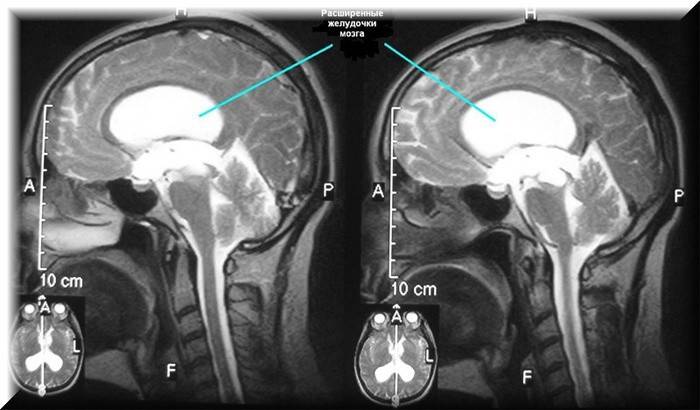

A hidrocefalia é uma doença na qual o líquido cefalorraquidiano se acumula na cabeça. Esta não é a água comum, mas o líquido cefalorraquidiano. Se, em crianças, a hidropisia é geralmente congênita, na qual a cabeça é aumentada, como pode ser visto na foto, em adultos ela aparece como resultado de doenças. A doença é muito difícil de detectar e alguns até morrem dela. A eficácia do tratamento da hidrocefalia cerebral em um adulto depende inteiramente do grau em que foi detectada. Cada tipo de hidropisia tem suas próprias manifestações características.

- Ressonância magnética Ajuda não apenas a verificar a exatidão do diagnóstico, mas também a determinar suas causas.